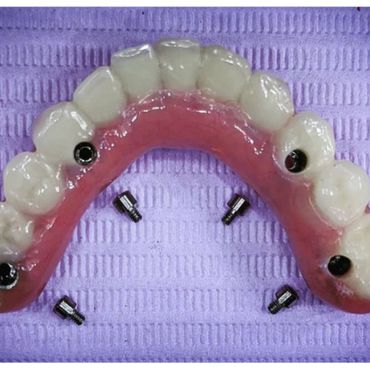

A dental implant is an artificial replacement of the root of a tooth. It is a viable option for people of all ages who are in good oral health. The implant is normally a cylinder-shaped metal post inserted and fused into the bone. A replacement tooth is then fitted onto it once it fuses into the bone. With the implant, one can eat, chew, and brush normally.

6. No need to remove and clean an appliance such as dentures.